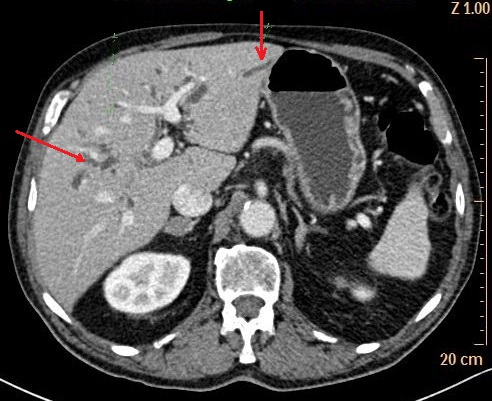

Aspects arrondies

hypodensite a bord irregulier de deux abces

angiocholite situe du foie droit (

fleche rouge ) . Image radiologique TDM avec

de contrast intraveineuse ( C+ ) en coupe

axiale . |

|

Image d'une pyleplebite de veine

mesenterique supperieure ( fleche jaune ) .

Sa paroi est epais et hyperdensite

etre en vue tres nette ( fleche jaune ) sur ce coupe . Image radiologique TDM en coupe

coronal ( frontal ) |